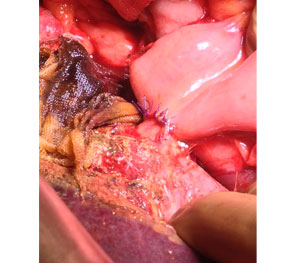

Intra Operative image after right hepatectomy